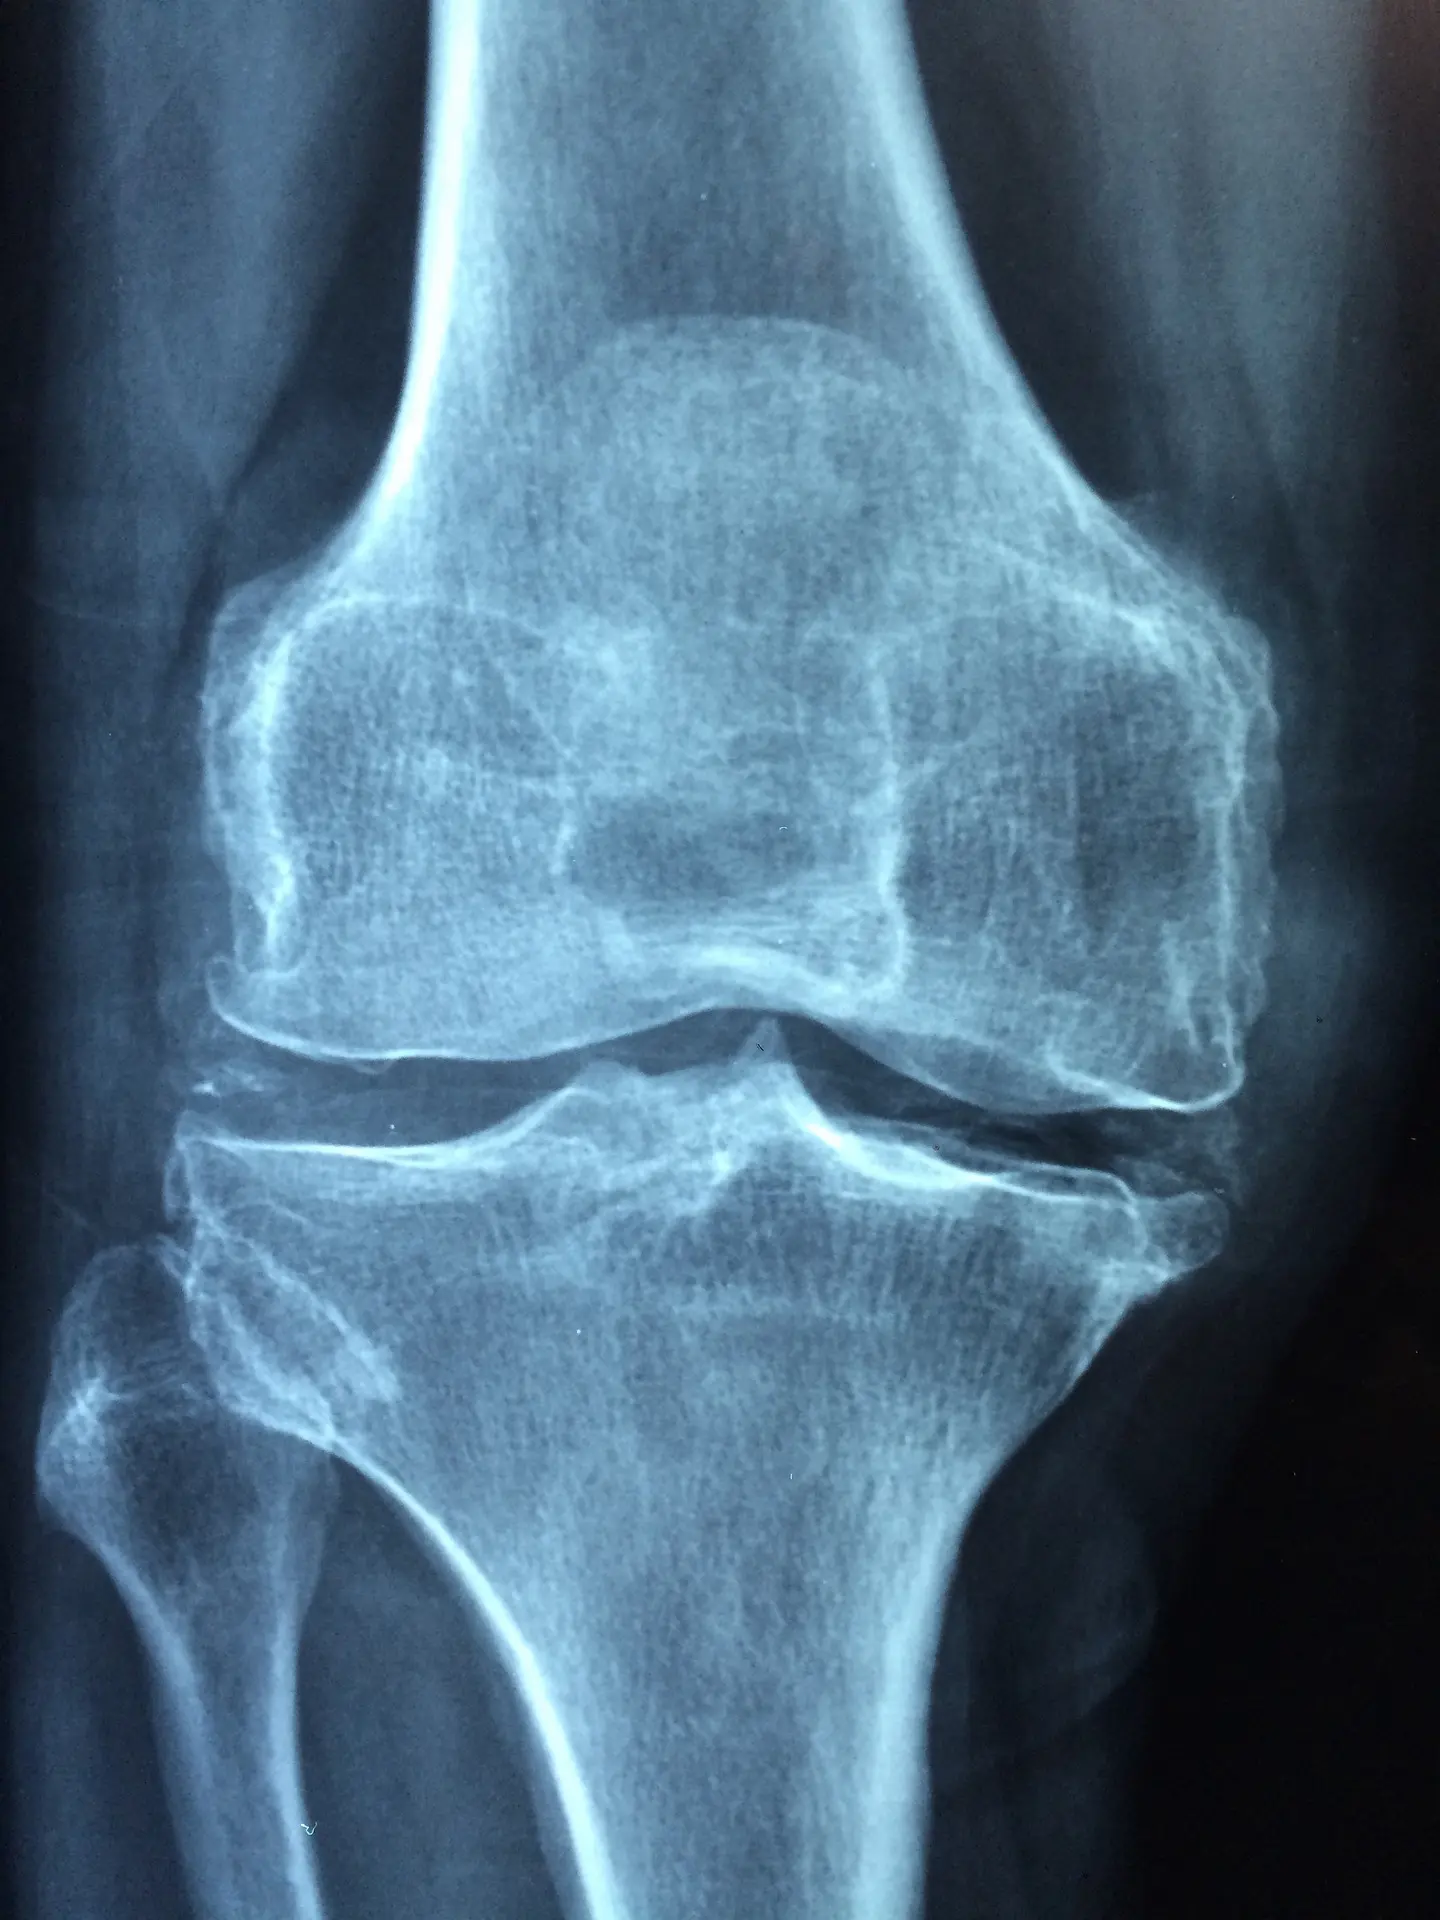

Badanie MR umożliwia ocenę uszkodzenia kości, nie tylko złamania i ewentualnego przemieszczenia odłamów kostnych, ale również stłuczenia i obrzęków wewnątrz kości oraz przeciążeniowych złamań podchrzęstnych niewidocznych w badaniach rentgenowskich. Badanie MR pozwala również na ocenę zmian zapalnych, martwiczych i zwyrodnieniowych w kościach i stawach.

Urządzenie posiada też specjalny program do nieinwazyjnego obrazowania zawartości wody w chrząstkach stawowych – CartiGram, niezwykle pomocny we wczesnym rozpoznawaniu zmian zwyrodnieniowych.